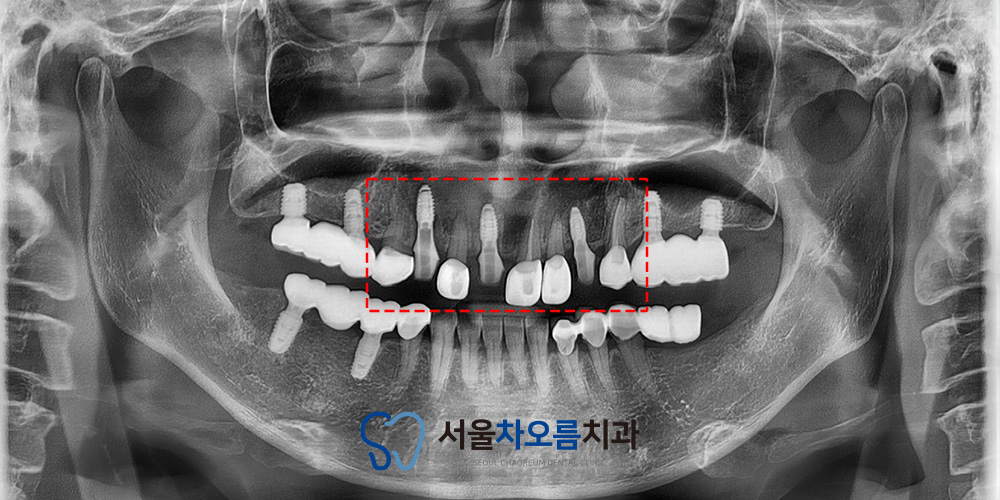

25.12.29

먼저 브릿지를 깨끗하게 제거 한 뒤

발치를 진행하고 임플란트 식립을

진행하였습니다.

임플란트는 식립 후

초기고정이 중요하기 때문에

한 달 동안은 임플란트에

무리한 힘이 가해지지 않도록

안정화 기간을 갖고,

잇몸과 뼈가 회복될 수 있도록

관리하였습니다.

이 기간 동안 임플란트가 잇몸뼈와

단단히 결합할 수 있도록

경과를 주기적으로 확인하였습니다.

이렇게 4개월 뒤

임플란트의 치유기간을 거친 뒤

특별한 문제 없이 다음 보철 단계로

진행할 수 있었습니다.